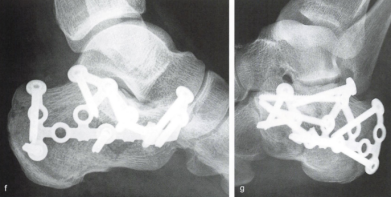

按照以往常规的治疗策略来看,少部分未累及关节面或跟骨高度、宽度无明显变化等的简单骨折可选择保守治疗(手法整复及石膏固定制动)。而大部分累积关节面或骨折碎裂、移位明显的跟骨骨折常常需手术治疗,否则患者后期很可能会面临创伤性关节炎、跟骨畸形愈合致创伤性扁平足等风险,从而导致患者出现长期跟部疼痛、穿鞋及行走困难等不良后果,严重影响患者日常生活及工作等。其中,对于关节面严重碎裂移位的复杂跟骨骨折,目前标准的手术方式是通过足跟外侧作一长“L”形皮肤切口行切开复位钢板螺钉内固定术。其优势在于暴露充分,直视下复位,复位效果好,远期并发创伤性关节炎及骨折畸形愈合风险相对较低。

回到前文所述的患者程某,其X线片及CT检查提示其骨折系波及关节面的严重粉碎性骨折,具有明确的手术指征。

在骨科中心主任吴超的带领下,团队采用了天玑Ⅱ骨科手术机器人为程某开展了微创手术治疗,该手术时间短、创伤小、出血少、透视次数少,同时实现了骨折块的解剖复位和精准的螺钉置入及固定;术后影像学显示患者关节面完全复位,螺钉位置良好,固定可靠。